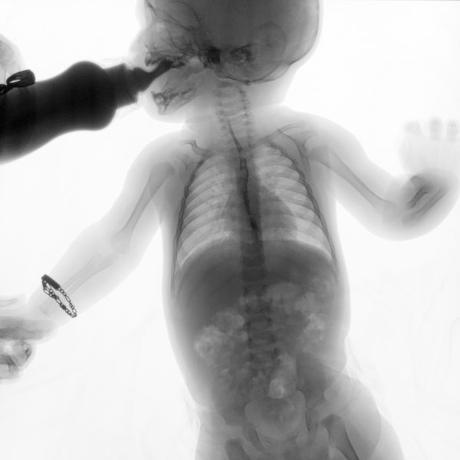

ESTUDIO SOLICITADO: SERIE ESOFAGOGASTRODUODENAL.

Se realiza Esofagograma con material de contraste baritado, por vía oral y por medio de control fluoroscópico se toman distintas proyecciones observando lo siguiente.

Se observa mecánica de la deglución con adecuado paso de medio de contraste de faringe a esófago sin presencia de defectos de llenado depósitos anómalos o fuga del mismo.

ESÓFAGO se observa de situación, calibre y trayecto normal. Contornos regulares y bien definidos. No se observan depósitos anómalos, defectos de llenado o fuga del medio de contraste.

UNION ESOFAGOGASTRICA se observa con calibre y situación normal. Sin observar reflujo a las maniobras de valsalva

ESTOMAGO se observa en su situación habitual, distendido, sin defectos de llenado.

- Actualmente no se demuestra Reflujo gastro-esofágico.

- Estudio de apariencia normal.